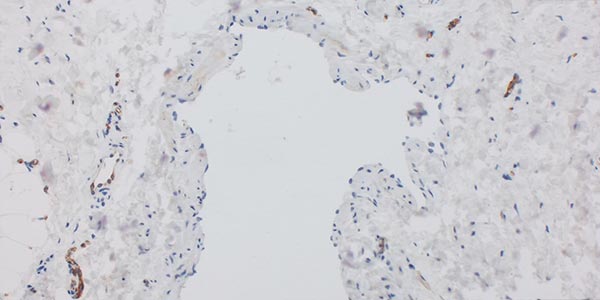

Immunhistochemische Färbung auf das Protein WT1 (Wilms Tumor 1), 200-fache Vergrößerung. Der Marker WT1 ist besonders hilfreich zur Unterscheidung von vaskulären Malformationen (keine endotheliale Positivität) und vaskulären Tumoren (Endothelien WT1-positiv). Eine Ausnahme bilden normale, proliferierende Gefäße und vor allem arteriovenöse Malformationen, die ebenfalls WT1-positive Endothelien aufweisen. An dem hier gezeigten Präparat ist gut die fehlende Anfärbung der Endothelien im fehlgebildeten Gefäßraum zu sehen, klarer Hinweis auf eine Gefäßmalformation (WT1-negativ). Normal ausgebildete, kapilläre Gefäße außenherum zeigen eine intensive zytoplasmatische braune WT1-Färbung, gutes Zeichen dafür, dass die Färbung technisch gut funktioniert hat.

Die histopathologische Aufarbeitung zeigte dann auch den typischen Befund einer benignen Gefäßläsion (CD31-positiv) mit dysplastischem, asymmetrisch unregelmäßigem Wandaufbau. Wie für solche Slow-flow-Gefäßmalformationen typisch, ist die glattmuskuläre Gefäßwand nicht überall gleich dick und symmetrisch ausgebildet, sondern fehlt zum Teil sogar ganz (SMA, EvG). Kaum Proliferation des beteiligten Gewebes (Ki67 sehr niedrig). Die fehlende WT1-Positivität der betroffenen Gefäßendothelien ist ein weiterer Hinweis auf eine Gefäßmalformation. Wesentlichstes histopathologisches Unterscheidungsmerkmal zwischen einer lymphatischen Malformation und einer venösen Malformation ist die immunhistochemische Anfärbung des Podoplanin der Gefäßendothelien der Läsion mittels des Antikörpers D2-40. Nur die Gefäßendothelzellen einer lymphatischen Malformation (D2-40 positiv) färben hier an. In dem Präparat zeigten sich zusätzlich auch multiple dysplastische Gefäßmalformationsareale, deren Gefäßendothel nicht mit D2-40 anfärbte, also handelte es sich hierbei um Anteile einer venösen Malformation. Die korrekte histopathologische Diagnose ist daher auch eine kombinierte venolymphatische Malformation. Die klinisch und in der Bildgebung klar im Vordergrund stehende lymphatische Komponente steht in dem Präparat der hier gewonnenen Stanzbiopsie aus der Läsion gegenüber der venösen Komponente eher im Hintergrund.